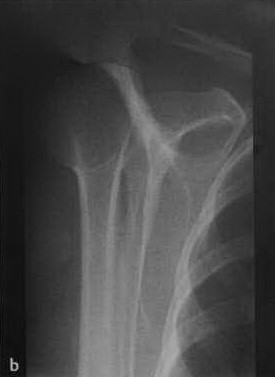

a,b Передний вывих плечевого сустава у женщины 46 лет после падения на вытянутую руку. (а) Рентгенологическое исследование праовго плечевого сустава в прямой проекции с ротацией противоположной стороны туловища на 40° кпереди и на (b) Y-проекция. Суставная впадина пуста. Передненижнее смещение головки плечевой кости ниже клювовидного отростка.

а, b Задний вывих плечевого сустава у женщины 45 лет после падения с велосипеда, (а) Рентгенологическое исследование правого плечевого сустава. Суставная щель в прямой проекции не визуализируется, плечо ротировано медиально.(b) Y-проекция четко демонстрирует задний вывих.